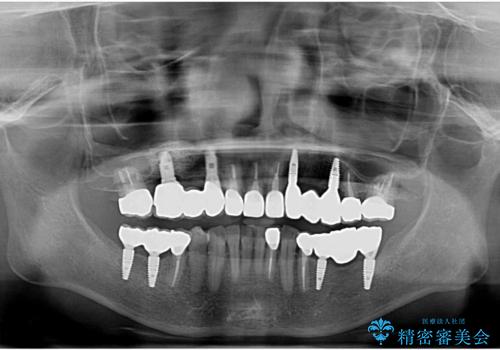

全顎的 虫歯治療 インプラント補綴

- 「他院で虫歯治療を行っているが、延々終わらず数年経過している。全体的な治療を希望したい。」と全顎的な治療を希望され来院されました。

・再発した虫歯

・銀歯の下にできた虫歯

・根尖性歯周炎

・残根状態の歯

など、虫歯を原因とする問題が多発した状態です。

今後延々と治療を繰り返さないために、全ての銀歯を外し虫歯を丁寧に取り切り、根管治療を行い、残せない歯は抜去を行った上でインプラント治療を行っていくことで全体的な治療を計画していくこととなりました。

工程数が多かったため治療期間はかかりましたが、しっかりと安定した噛み合わせ、審美的な口腔内環境を達成することができ大変満足していただくことができました。